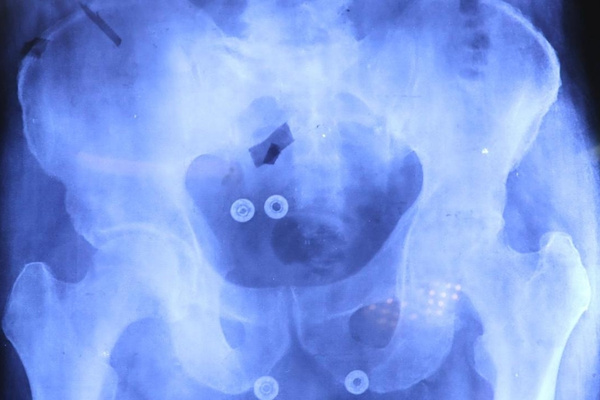

CIUDAD DE PUEBLA.- En un esfuerzo conjunto, el Sistema Estatal para el Desarrollo Integral de la Familia (SEDIF), la Beneficencia Pública del Gobierno de México, IMSS-Bienestar y la Secretaría de Salud, iniciaron las cirugías de prótesis de cadera y rodilla para pacientes mayores de 60 años. Durante el fin de semana se realizaron las primeras tres intervenciones quirúrgicas que marcan el comienzo de una serie de procedimientos que buscan mejorar la calidad de vida de los beneficiarios.

El equipo de cirujanos del IMSS- Bienestar comentó que la meta de las operaciones de cadera y rodilla, es que las y los pacientes recuperen la movilidad y funcionalidad; se reduzca el dolor y limitaciones físicas, así como mejorar la calidad de vida y oportunidades de desarrollo personal.

José Francisco González y Javier Sandoval Ventura son ejemplo de cómo las prótesis apoyan a los grupos vulnerables. Estos primeros pacientes beneficiados llevaban más de un quinquenio en espera para ser intervenidos en su rodilla y cadera, respectivamente.